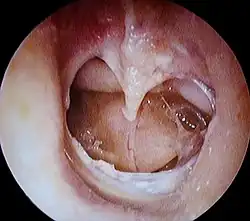

| A completely perforated eardrum, showing the handle of the malleus (hammer bone). | |

A perforated eardrum (tympanic membrane perforation) is a prick in the eardrum. It can be caused by infection (otitis media), trauma, overpressure (loud noise), inappropriate ear clearing, and changes in middle ear pressure. An otoscope can be used to view the eardrum to diagnose a perforation. Perforations may heal naturally or require surgery.

An otoscope can be used to look at the ear canal. This gives a view of the ear canal and eardrum, so that a perforated eardrum can be seen. Tympanometry may also be used.[6]